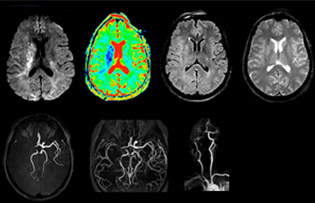

“The biggest challenges are properly characterizing the lesion and giving the surgeon all the information needed, such as the location of vessels and functional areas. Sometimes a very comprehensive exam is necessary, such as when a mass has been discovered at another hospital after which the patient is referred to us. We then do both lesion characterization and preoperative imaging in one exam, so both morphologic and functional assessment. For morphologic assessment we will use pre- and post-contrast T1-weighted imaging, FLAIR to assess infiltration, and diffusion. For functional characterization we will perform perfusion, spectroscopy, and susceptibility weighted imaging to look for micro vessels or micro hemorrhage inside the lesion[4]. For preoperative imaging we perform specific morphologic imaging that is compatible with the navigation system; depending on the location of the tumor, we would do fMRI or DTI.”

“In France, every stroke is usually imaged with MRI, not CT, even for emergency treatment.” “In France, stroke is usually imaged with MRI, not CT, even for emergency treatment. This is because MRI helps us directly visualize ischemia in the acute phase, but can also help rule out differentials such as MS and hematoma. In addition, we can assess the intracranial and extracranial vessels during the same examination,” says Dr. Savatovsky.

“Ingenia provides great flexibility in the parameters setting. We can tune a sequence the way we want,” says Dr. Savatovsky. “For example, in a stroke exam we use a FLAIR sequence of about two minutes instead of the four-minute FLAIR we use for MS. The diffusion is 30 seconds, the T2*-weighted scan is 30 seconds, the angiography scan time is less than one minute. Ingenia is a great scanner in that situation; even with these fast sequences we can achieve good images with good SNR. When the first sequence tells us that it’s not an ischemic stroke but a hemorrhagic stroke, we may switch to a time-resolved angiography to look for vascular malformations and venous thrombosis.

“Every center is different, but for me the ideal protocol for stroke includes diffusion weighted imaging, FLAIR, and fast susceptibility imaging,” says Dr. Savatovsky. “Our fast susceptibility weighted imaging takes 50 seconds, so it’s as fast as T2*-weighted imaging. It visualizes hemorrhage but also the clots. We also do 3D MR angiography that provides information on cervical and brain vessels. If the patient does not need immediate treatment, or if additional information is needed to decide on treatment, we might also add perfusion imaging and post-contrast T1-weighted imaging.”